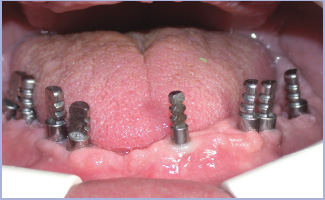

Le successive fasi protesiche sono state condotte con le metodiche convenzionali ed hanno portato all’allestimento di un manufatto protesico di 24 elementi (figg. 10-26).

- Figg. 19, 20, 21, 22 – Prova intraorale dei monconi e delle sovrastrutture protesiche

- Fig. 20

- Fig. 21

- Fig. 22